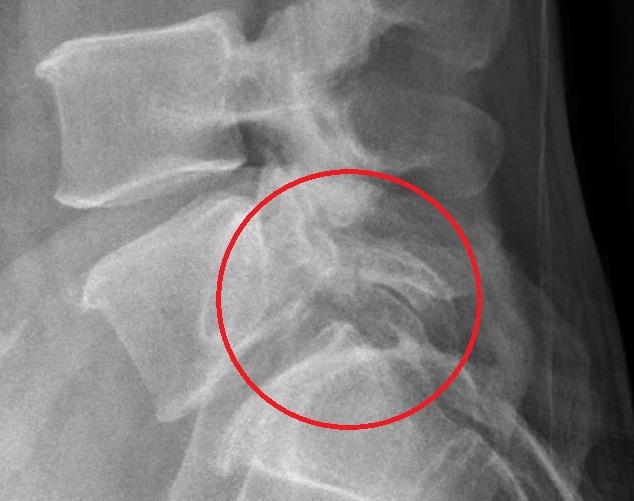

男子腰椎第5節椎弓骨折,經醫院以水介質震波治療,紓解其腰痛,也解決了導致腸躁及頻尿的問題。圖/活力得中山脊椎外科醫院提供

「活力得中山脊椎外科醫院」院長楊椒喬指出,患者曾經意外跌倒,常下背疼痛,在北部醫院就醫,檢查發現腰椎第5節有椎弓骨折,又患者說有腸躁與頻尿的困擾,且經過不同科別檢查與治療,卻未能有效改善其疼痛。

楊椒喬說,患者接受每周一次約4000發的高能量骨癒合震波,前後共8次治療,他的椎弓骨折處已出現明顯生長讓骨折處癒合,除了紓解腰痛,連帶惱人的腸躁與頻尿的問題,都一併解決,不再困擾他。後續並持續再接受2次治療,以完整的療程達到骨癒合的療效。